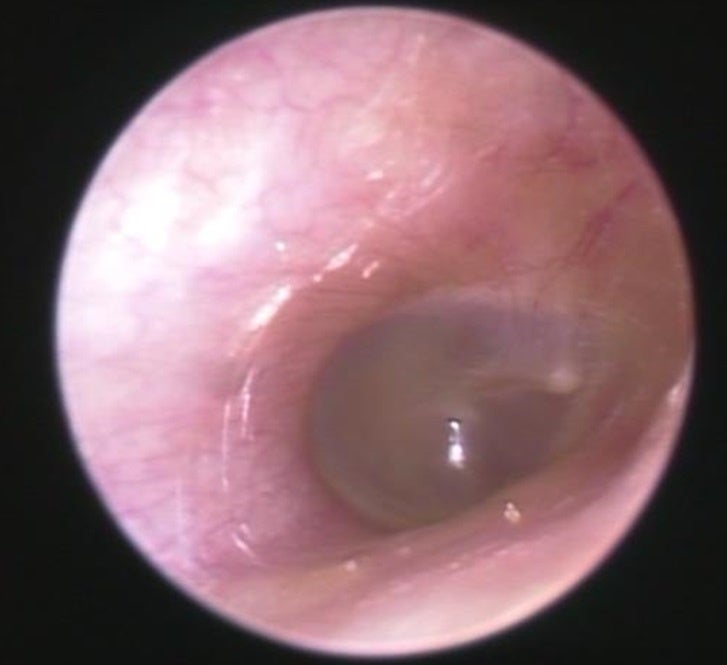

■外耳炎や外耳道真菌症(耳カビ)についても解説

『外耳炎は、耳の入り口から鼓膜までの「外耳道」と呼ばれる部分の皮膚に細菌が繁殖しておきる病気です。真菌(カビ)が繁殖すると、外耳道真菌症(耳カビ)になります。発症リスクが上がる原因のひとつとして「密閉型イヤホンの長時間使用」が挙げられます。

主な症状は、かゆみ、痛み、耳が詰まったような感じ、聞こえにくさです。特にかゆみは薬で治療しないとサイクルから抜け出せません。温度が20~30度、湿度が60%以上、風通しが悪く日陰だとこのようなカビが繁殖することがあります。密閉型のイヤホンを長時間装着すると、このようなカビができるリスクが高まります。治療法として、外来でカビを掃除して薬を塗ることを繰り返し行いますが、1ヶ月~数ヶ月かかることも稀ではありません。

耳のトラブルを放置すると、治りにくくなる、聴力が低下する、さらに悪化してしまい中耳や内耳、悪性外耳道炎などの重篤な病気が進行してしまう場合もあります。痒みや違和感は無理せずケアをしましょう。』と医師の観点から解説していただきました。